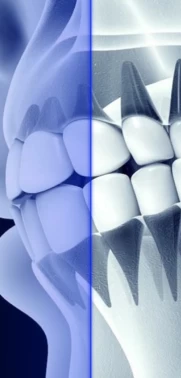

Стадии пародонтита

Здоровый зуб |

1 стадия |

2 стадия |

3 стадия |

4 стадия |